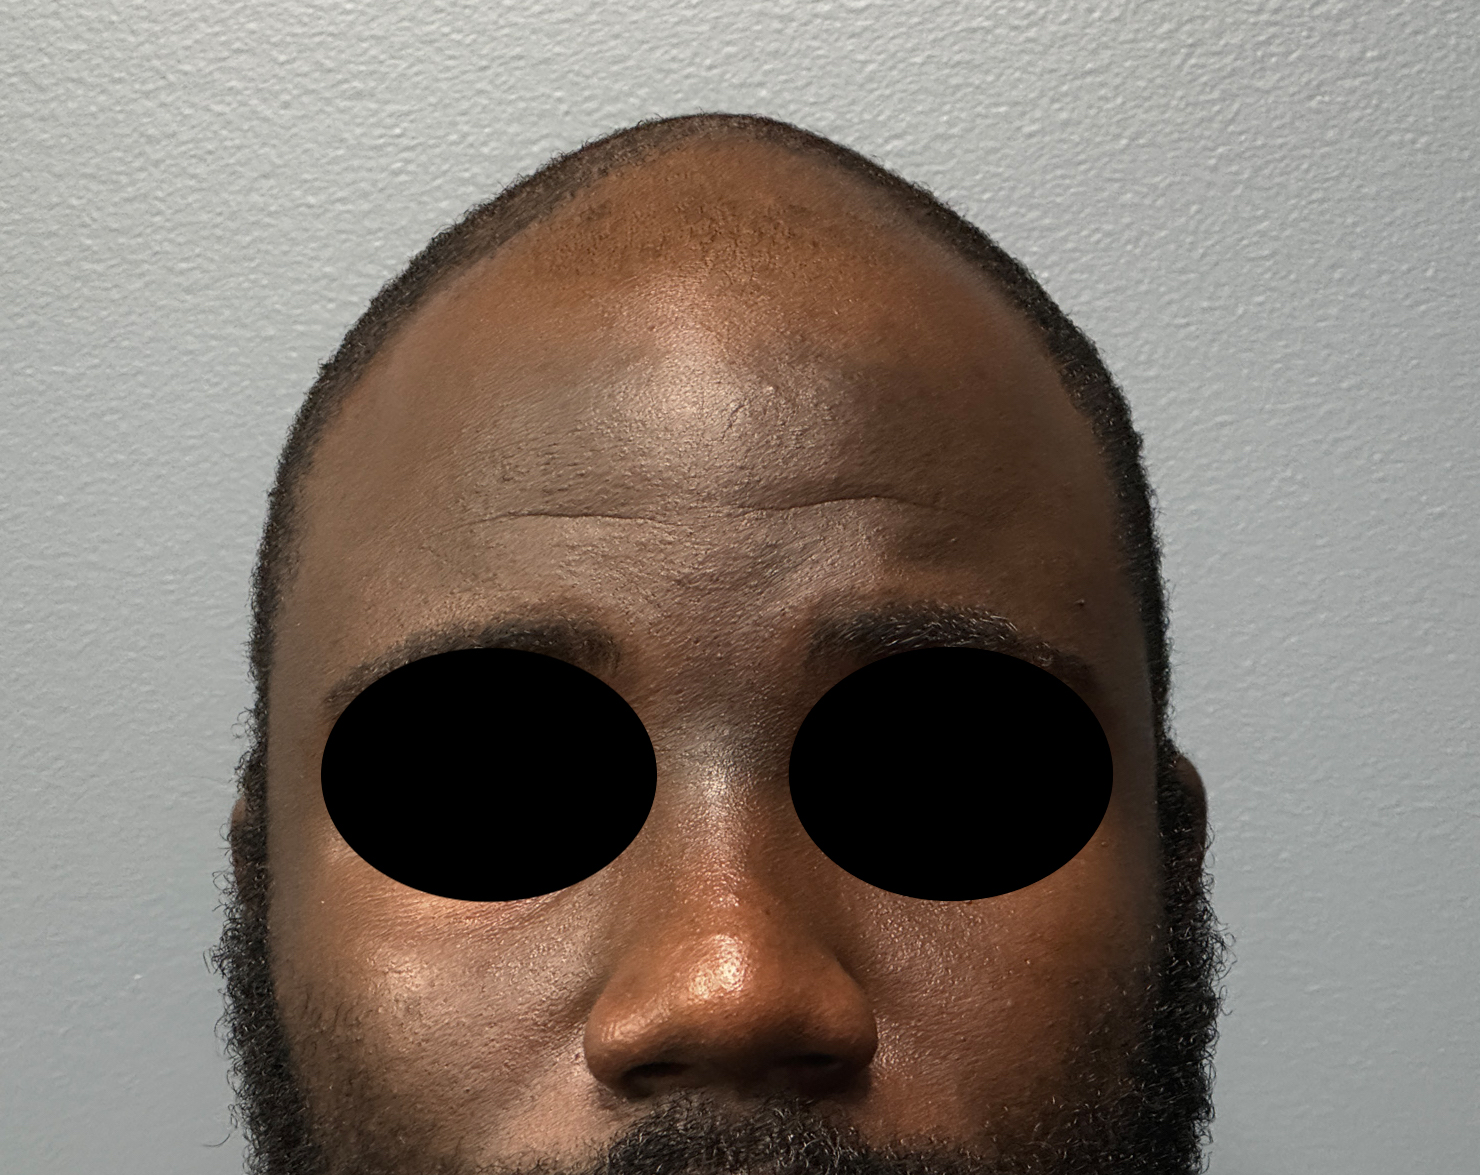

Patient 51

Desire for improved head shape that has a less peaked shape.

Placement of custom skull implant.

Desire for improved head shape that has a less peaked shape.

Placement of custom skull implant.